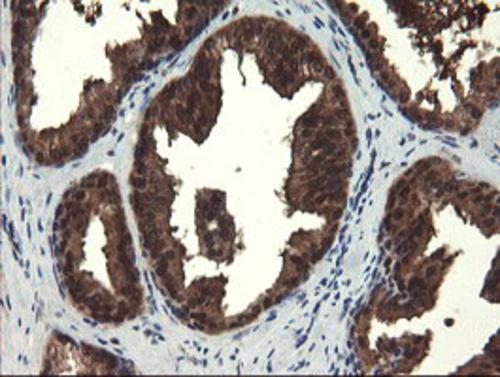

Immunohistochemical staining of paraffin-embedded Human prostate tissue within the normal limits using anti-MPI mouse monoclonal antibody. (Heat-induced epitope retrieval by 10mM citric buffer, pH6.0, 100°C for 10min, BD-PE1520)